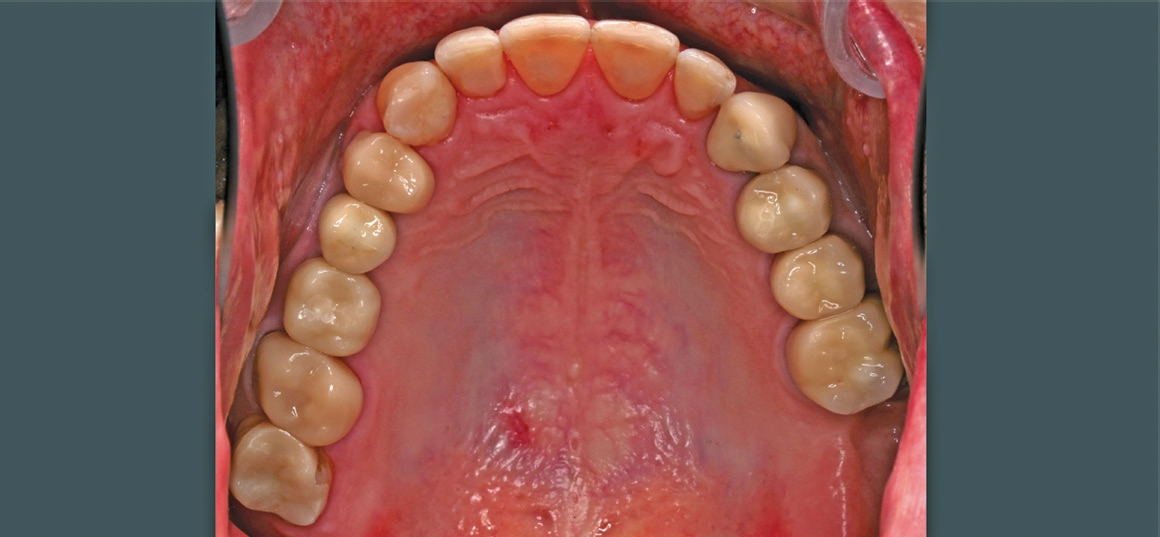

Patient 3: weiblich, 62 Jahre alt, Anamnese: unauffällig; spezielle Anamnese: Zustand nach chronischer schwerer Parodontitis; Diagnose: nicht erhaltungswürdiger Zahn 16, Freiendsituation. Knochenersatzmaterial: maxgraft® (botiss) (Abb. 13 bis 15).